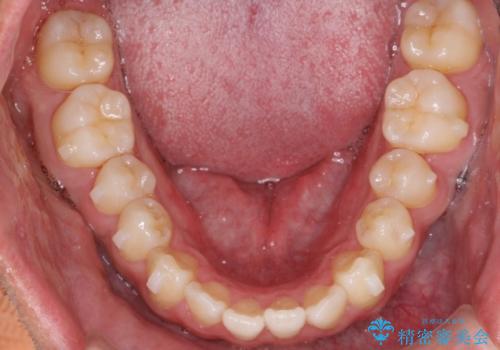

前歯が反対にかんでいる インビザラインとワイヤーを組み合わせた矯正治療

- 前歯が正常とは反対にかんでいるとのことで、来院されました。

患者様がマウスピースを希望されていましたが、上の前歯のがたつきを先にワイヤーで改善する方が早く治療が終了することが可能であるとお伝えし、上顎のみ半年間ワイヤーで治療を行いました。

マウスピースのみでの治療も可能でしたが、治療期間がもう少し延長していた可能性があります。